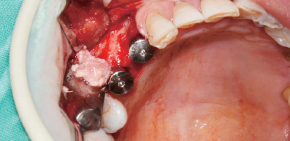

Caso clínico utilizando fresa de obtención Ø3.5/4.0.

by Dr. Soohong Kim, DDS, Ph.D

Se realizó fresado a 300 RPM luego de marcar posición del sitio de implante y obtención.

La pantalla de silicona se llevó a contacto íntimo con los distintos niveles de hueso para prevenir la pérdida de limalla de hueso.

El hueso obtenido se observa con facilidad a través de la pantalla de silicona transparente.

El hueso se transfirió a un frasco luego de desensamblar la pantalla de silicona y stopper.

La cantidad de hueso fue mucho más que la esperada.

Luego de la instalación del implante, se conectan los pilares de cicatrización y se lleva a cabo la regeneración ósea en el defecto.